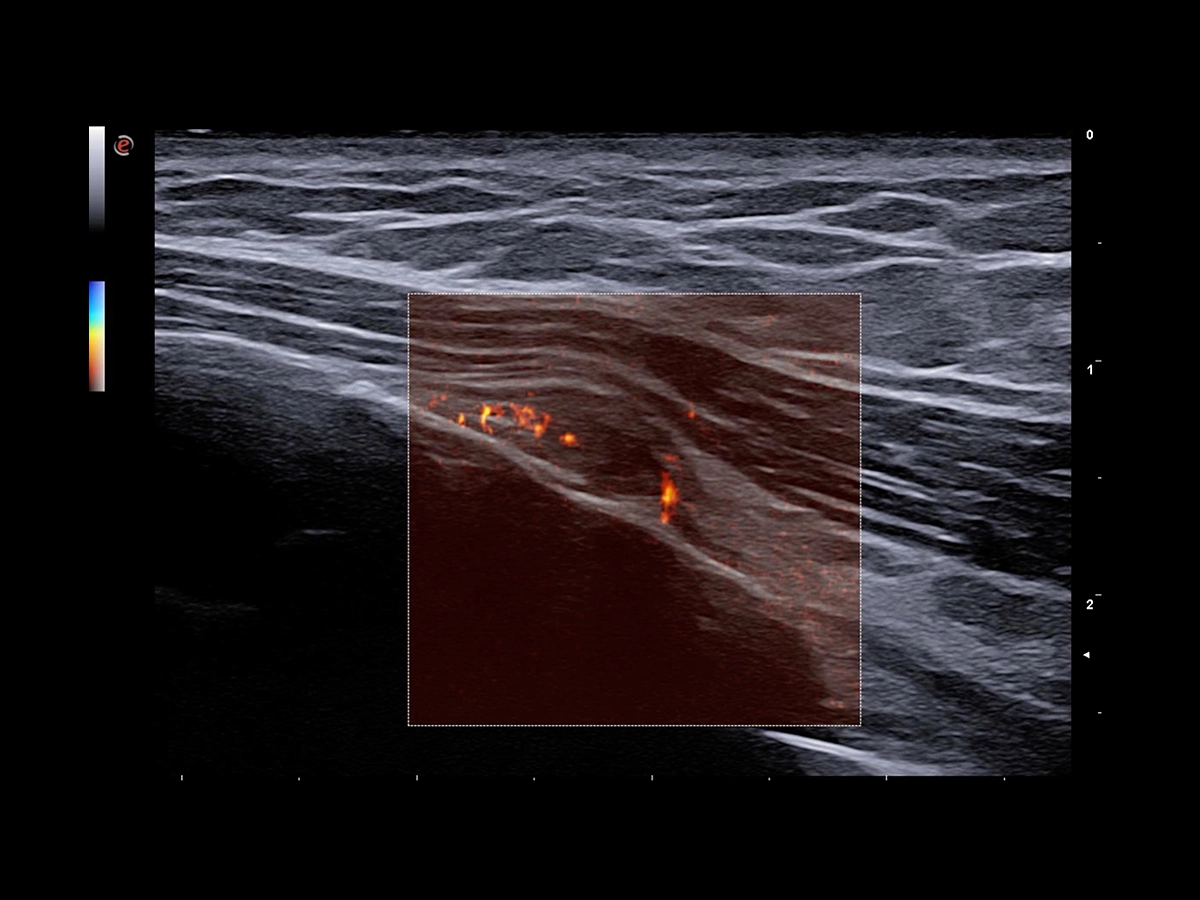

Doppler technology, with high sensitivity, is essential in any inflammation process where it is crucial to analyse slow flows.

The extreme sensitivity of Esaote Power Doppler technology is designed for the detection of low flow in small and superficial vessels. This improved vascular image quality, provided by Esaote, has positive impacts on diagnosis and therapy planning. Moreover, Esaote pushes the limits of microvascularization imaging one step further, with the latest implementation of microV technology to detect the smallest flow, bringing precious clinical value in the early detection, diagnosis and follow-up of musculoskeletal injuries or lesions characterization. Thanks to BrightFlow Technology, 3D rendering can be applied to all colour modalities to enhance vessel visualization.